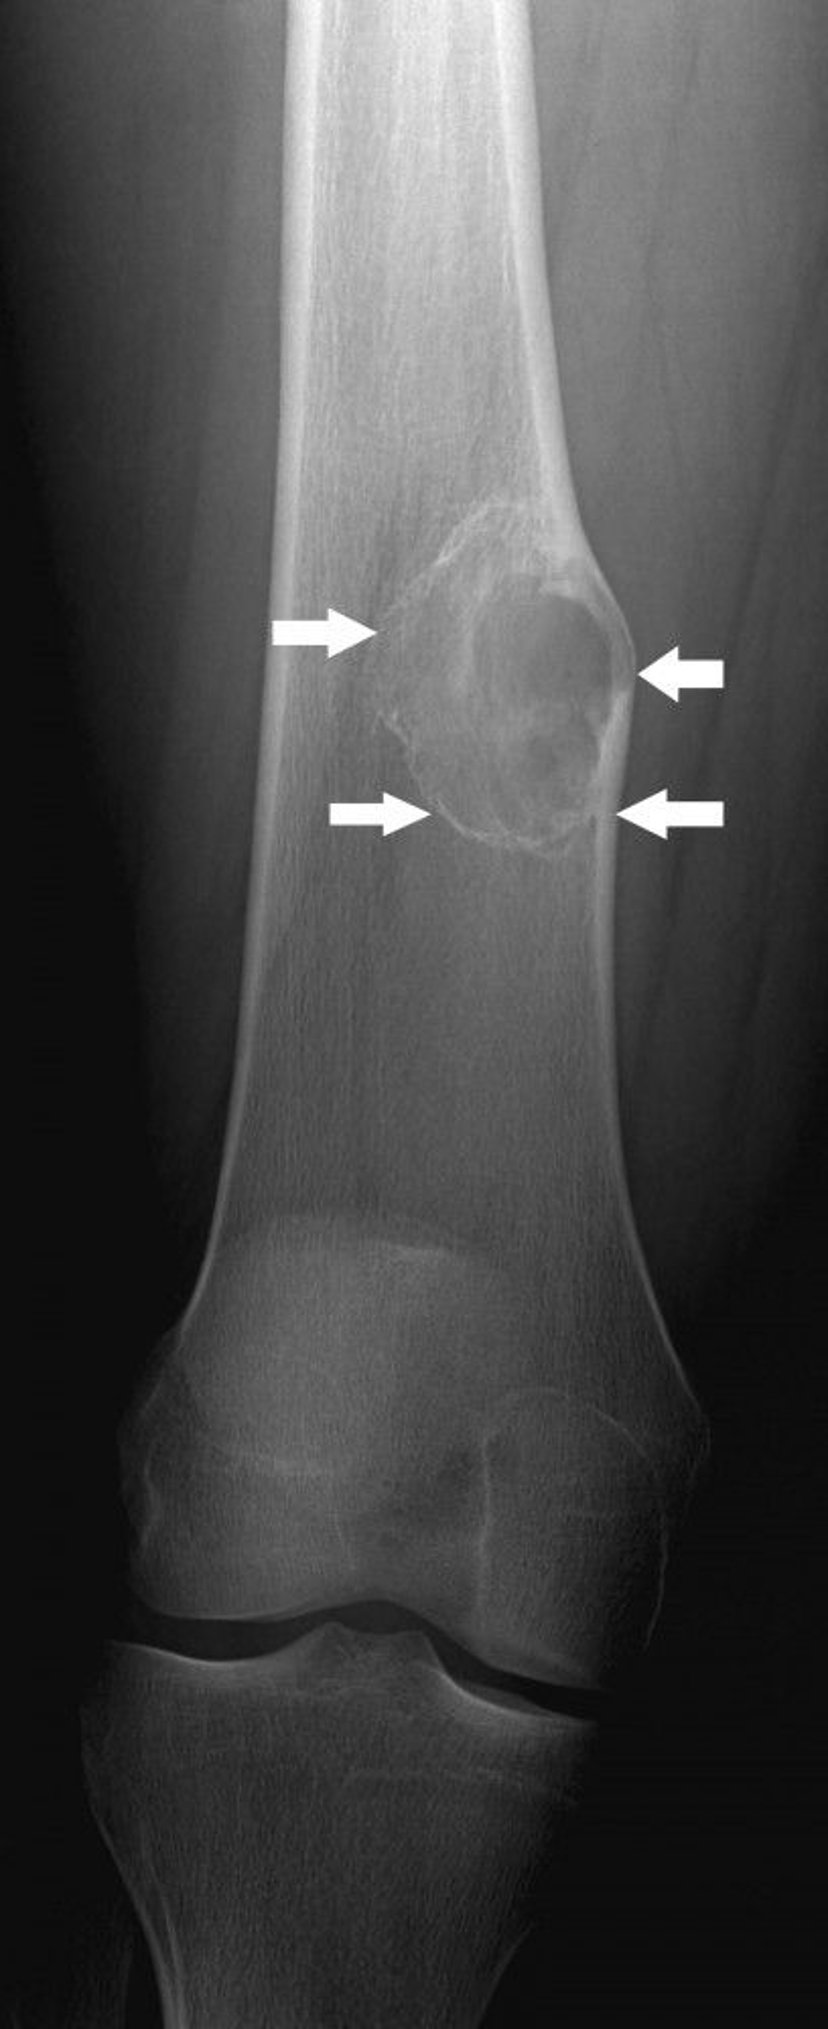

Nonossifying Fibroma

This radiograph shows a bone lesion (arrows) above the knee in the femur with mild expansion, which is typical of nonossifying fibroma.

Image courtesy of Michael J. Joyce, MD, and Hakan Ilaslan, MD.